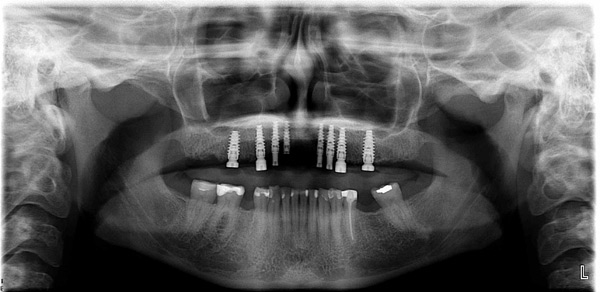

Case Study 11

Problem: This patient comes in with badly broken-down teeth and periodontal disease. Her midline is off center. She wants something that will be anchored in so she can eat well and look fabulous.

Plan: Our plan… we removed the remaining teeth and placed four implants on the lower for a fixed/hybrid prosthesis. The upper required bone grafting and then placed eight implants that will support a connector bar prosthesis.

She is happy. We’re happy. Mission accomplished!